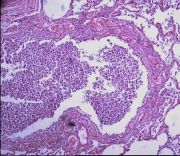

| 2021年12月10日 (五) 13:22 | 24号切片-小叶性肺炎-镜下观2-见细支气管.jpg (文件) |  |

209 KB | Cirno.9 | 基于MsUpload的文件上传 | 1 |